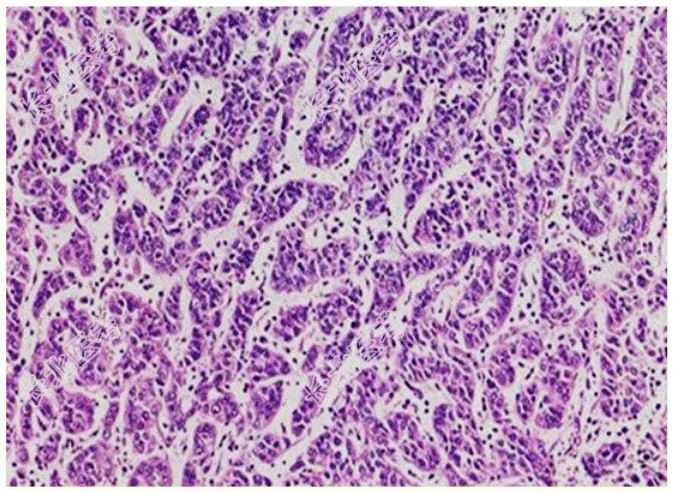

- [材料题] 患者女,63岁,胃体部发现一个直径约1.5 cm的肿块,呈息肉状生长,表面黏膜大多光滑,局部见浅表溃疡形成。切面见肿块呈灰白、灰黄色,位于黏膜下,界限尚清。光镜下组织形态如图所示。临床诊断为神经内分泌肿瘤。